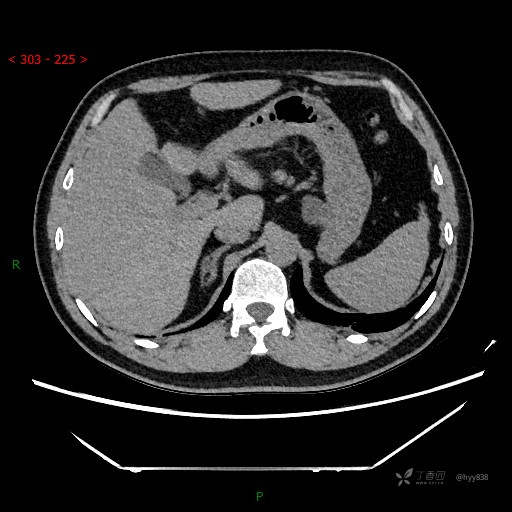

腹部CT平扫